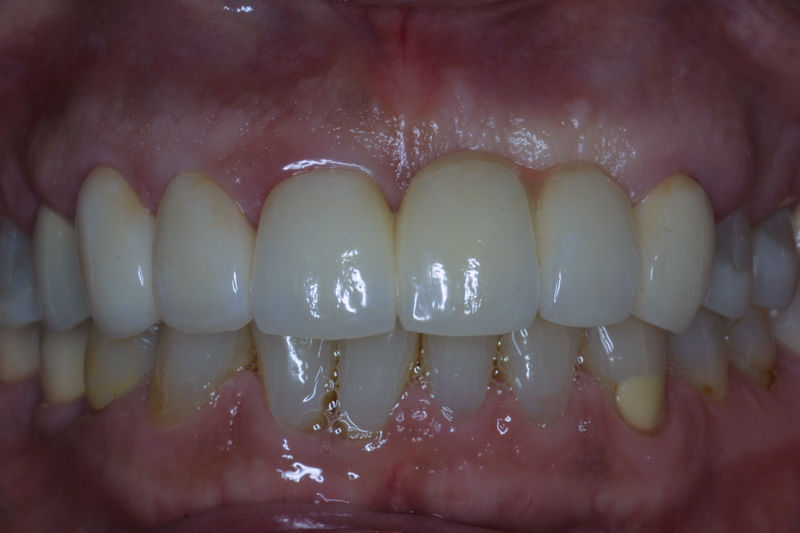

Amplia gama de tratamientos para mejorar la apariencia de la sonrisa, corrigiendo el color, la forma, el tamaño, la alineación y la posición de los dientes. Los procedimientos más comunes y solicitados incluyen el blanqueamiento dental, las carillas y coronas, así como las resinas.

Son restauraciones que cubren toda la cara frontal del diente, generalmente empleadas en el sector anterior y cuya finalidad es primariamente estética.

Ortodoncia y coronas.